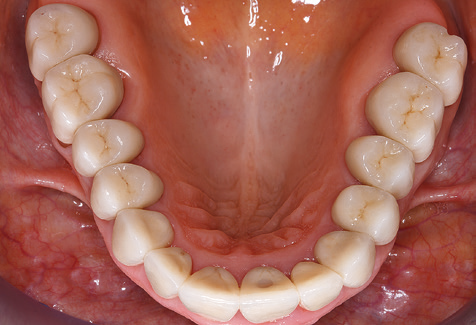

Nach der maschinellen Reinigung der Zahn und Implantatoberflächen erfolgt eine manuelle Instrumentierung der natürlichen Zahnoberflächen mit konventionellen Handinstrumenten. Bei der manuellen Reinigung ist insbesondere auf einen korrekten Anstellwinkel, eine ausreichende Schärfe, eine gute Abstützung und auf eine von apikal nach koronal gerichtete Arbeitsweise der Kürette zu achten. Zur Nachinstrumentierung der Implantatkonstruktionen sollten entweder Titan oder Carbonküretten verwendet werden (Abb. 8). Ergänzend zum Einsatz von Ultraschallgeräten können in der Erhaltungstherapie auch Pulverstrahlgeräte genutzt werden. Dabei ist jedoch zu berücksichtigen, dass diese Verfahren nicht zum Entfernen harter Beläge geeignet sind und daher die Verwendung von Hand oder Ultraschallinstrumenten nicht komplett ersetzen können. Abschließend erfolgt in jedem Fall eine mechanische Politur der zugänglichen Zahn und Implantatoberflächen mit Polierkelchen und Polierpasten (Abb. 9).

Für den klinischen Langzeiterfolg des parodontal kompromittierten Patienten ist die standardisierte und regelmäßige risikoadaptierte Betreuung im Rahmen der UPT der zentrale Baustein des Behandlungserfolgs. Dies gilt in besonderer Weise für Patienten, die nach erfolgreich abgeschlossener parodontaler Sanierung mit Implantaten versorgt wurden (Abb. 11a und b).